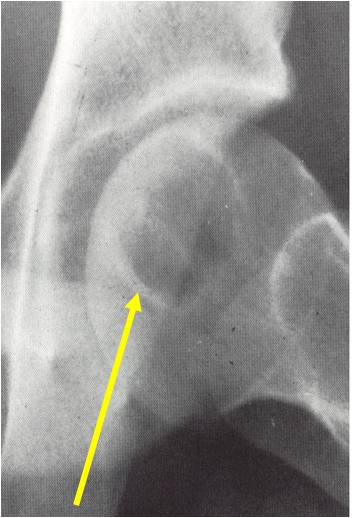

Sites:

- Epiphyses of long bones

- Most commonly proximal femur, proximal humerus, distal femur, proximal tibia

Radiographic Presentation

- Usually osteolytic, expansile lesion

- May be focally calcified

- Often a sharp interface between tumor and surrounding bone

- Sclerotic rim is uncommon

- Overlying cortex is usually thin, but intact